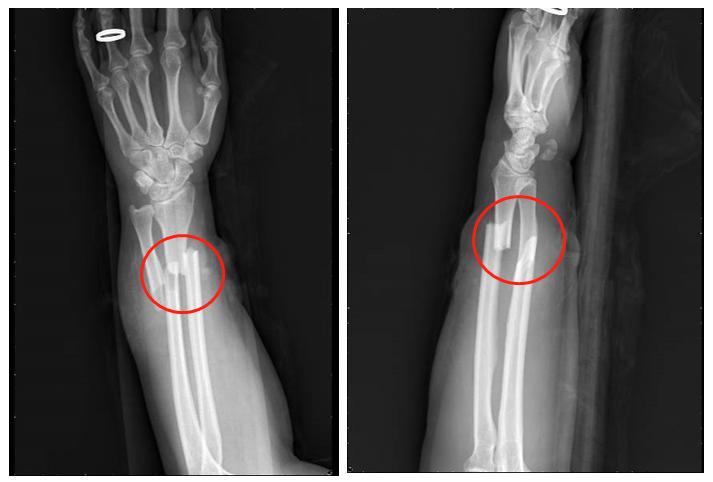

下面给大家介绍一个比较经典的病例,这是一个女性患者,由于机器挤压,导致导致前臂的尺骨和桡骨出现了双骨折,由于局部的皮肤剥脱比较严重,因此选择了钢板固定桡骨,尺骨选择闭合复位的弹性钉固定的治疗方案。

(初次受伤X线片)

(清除坏死皮肤,桡骨钢板内固定,尺骨闭合复位弹性钉内固定,皮瓣修复创面)

但很不幸的是,病人在手术后6个月和9个月复查的时候拍片发现尺骨的骨折间隙非常明显,骨头没有长到一起,这在骨不连的分类上属于传统意义上的扭转楔形骨不连。传统观念认为这种类型骨不连局部的生物活性是非常差的,所以只能选择植骨的手术方式。

(术后6个月)

(术后9个月)